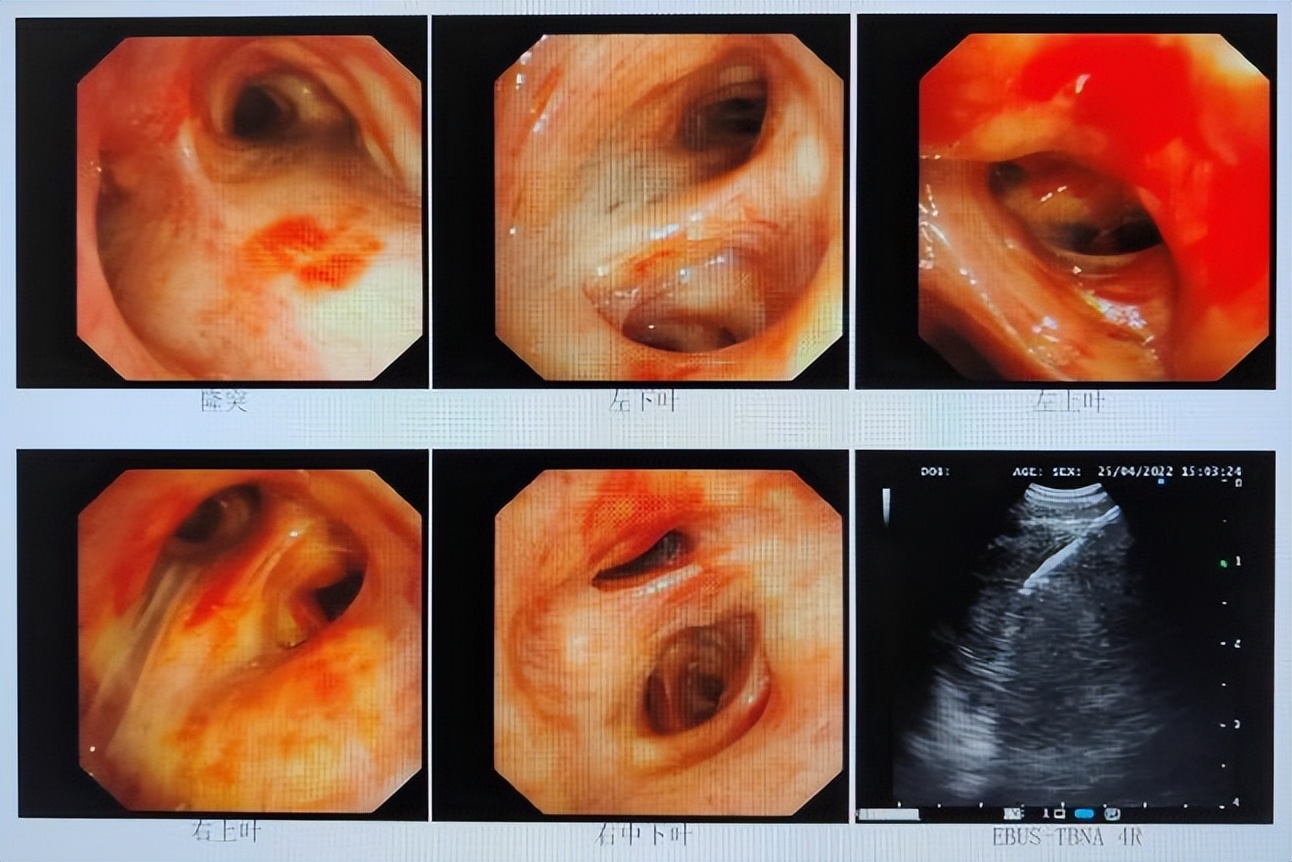

2022年4月22日支气管镜检查:1.左上叶病变:Ca?其他 2.纵隔肺门淋巴结增大(EBUS探及)。病检:涂片、5/4R、7组淋巴结EBUS-TBNA;6/左上叶。

2022年4月23日支气管镜下活检病理结果:左上叶慢性炎,鳞状上皮增生,上皮下纤维组织增生,4R/7组淋巴结穿刺活检不排除淋巴造血系统来源肿瘤。

2022年5月10日行超声引导下右肺肿块穿刺活检,病理诊断:(右肺)小细胞癌。

免疫组化结果:CD56(+),Ki67(60%+),CgA(+),TTF-1(+),Syn(+),P40(-),Napsin-A(-),CD5/6(-),CK(Pan)(+),LCA(-)。